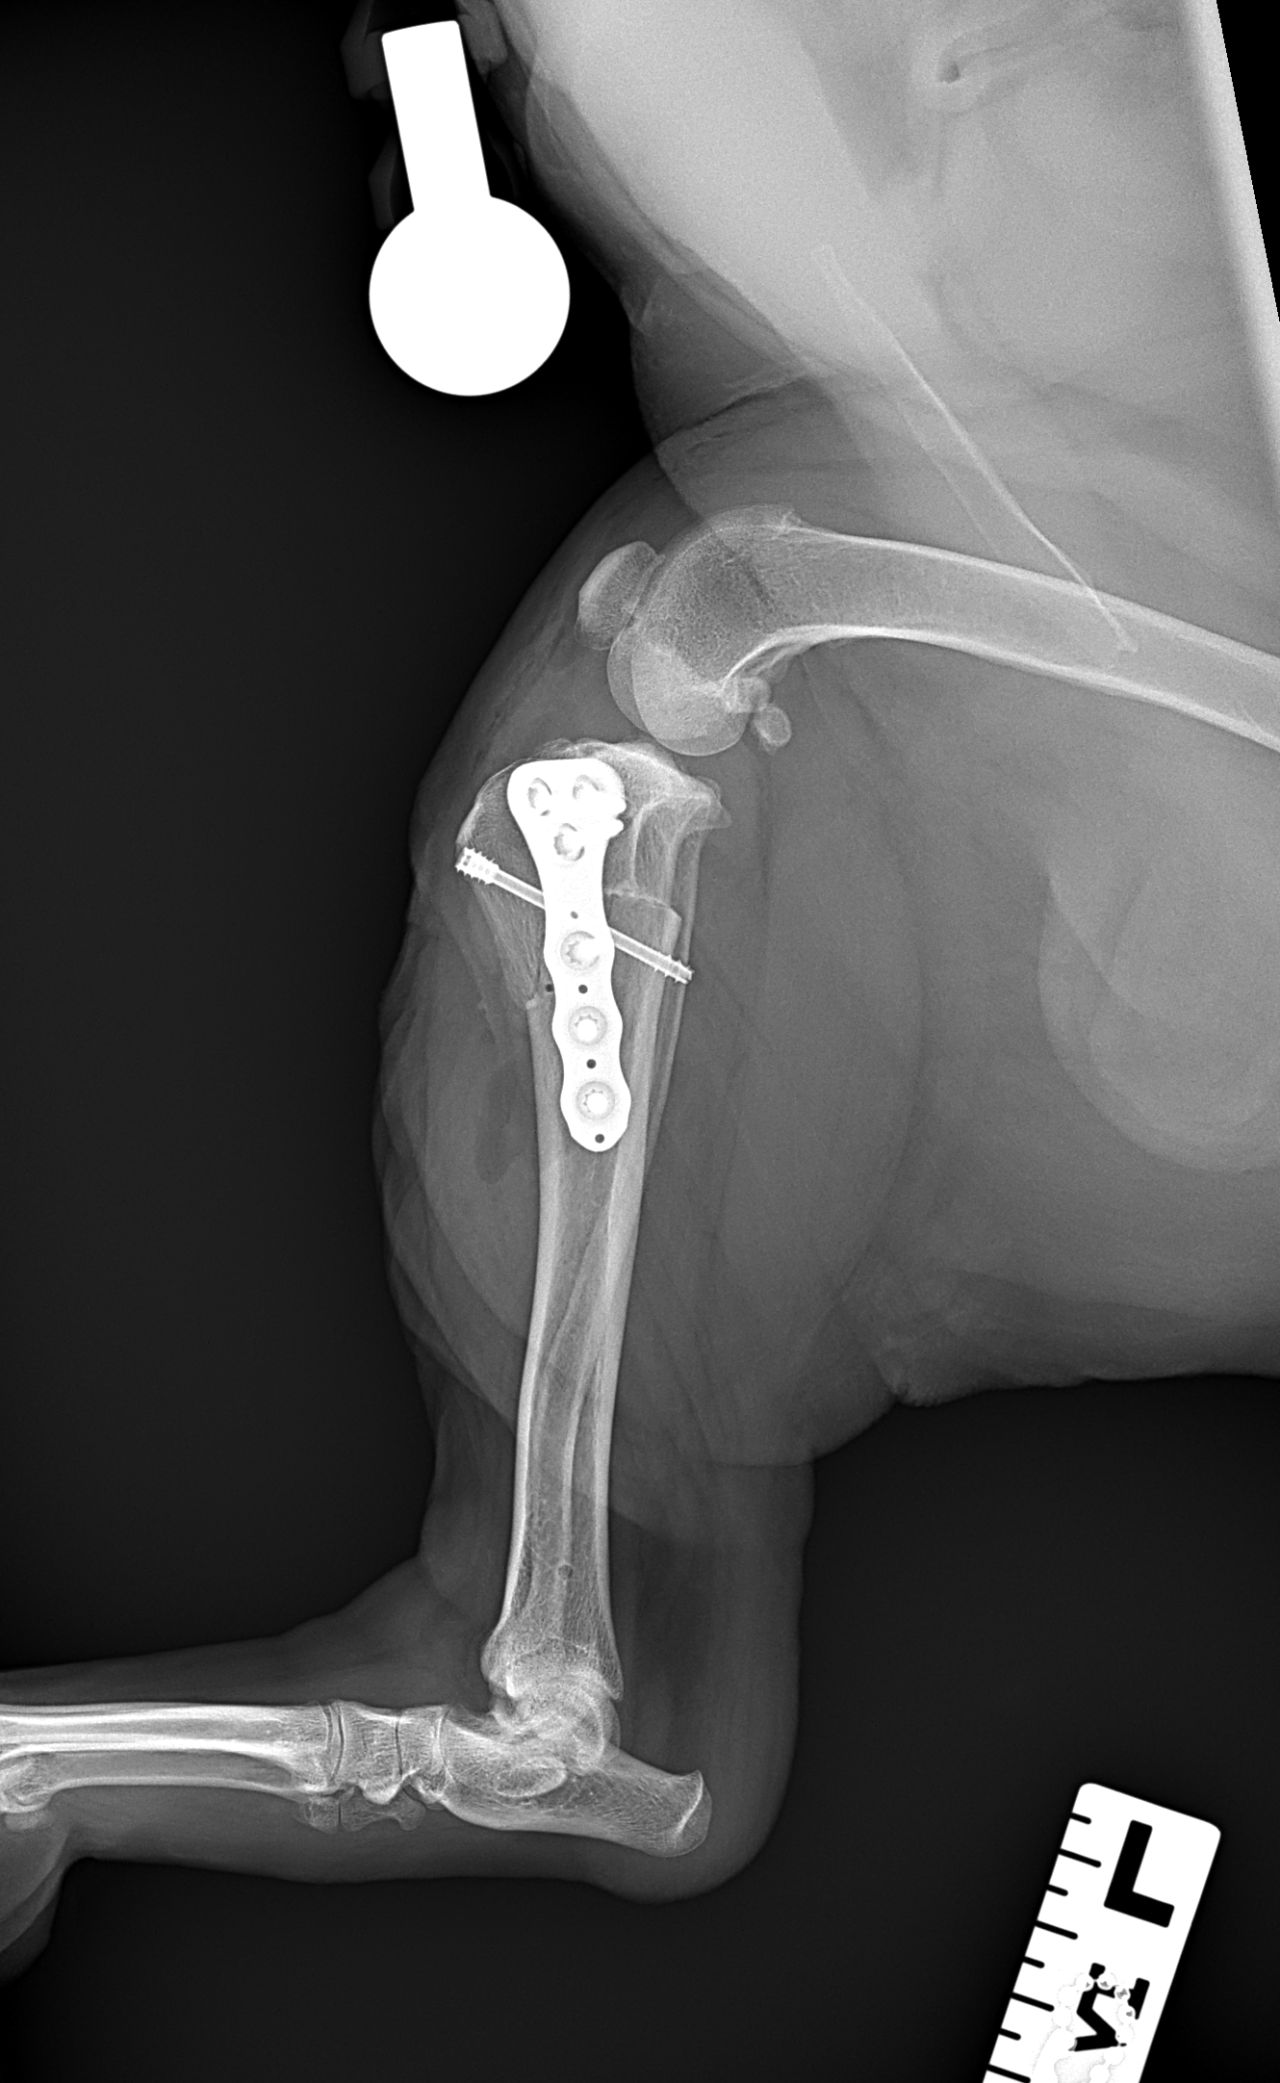

性の前十字靭帯断裂の中型犬にCBLOで安定化を実施しました。慢性経過のためミディアルバトレスが分厚くなって触知することが可能です。また関節内を探査すると、内側半月板の尾側領域はダブルバケットハンドルという状態で亀裂が2ヶ所確認されました。しばらくは安静が必要です。